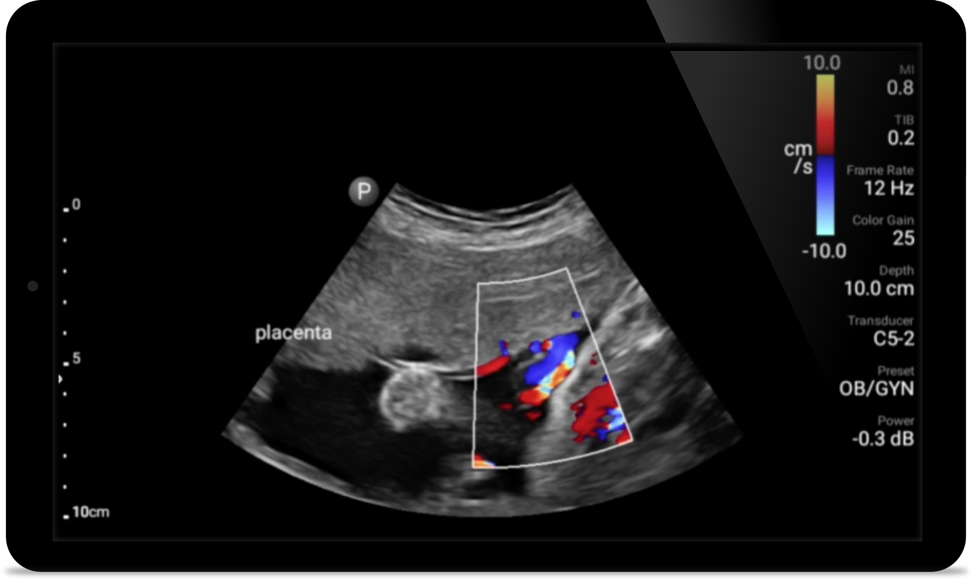

Bring ultrasound bedside

Using Lumify at your patients bedside can be a valuable tool to determine the status of stomach contents and can lower the risk of pulmonary aspiration. Together, this can reduce the risk of anesthesia complications.

Broadband phased array transducer

Lumify S4-1 broadband phased array transducer

• 4 to 1 MHz extended operating frequency range

• 2D, color Doppler, M-mode, advanced XRES and multivariate harmonic imaging

• High-resolution imaging for abdominal and cardiac applications: Cardiac, OB/GYN, Lung, Abdomen and FAST imaging preset optimizations